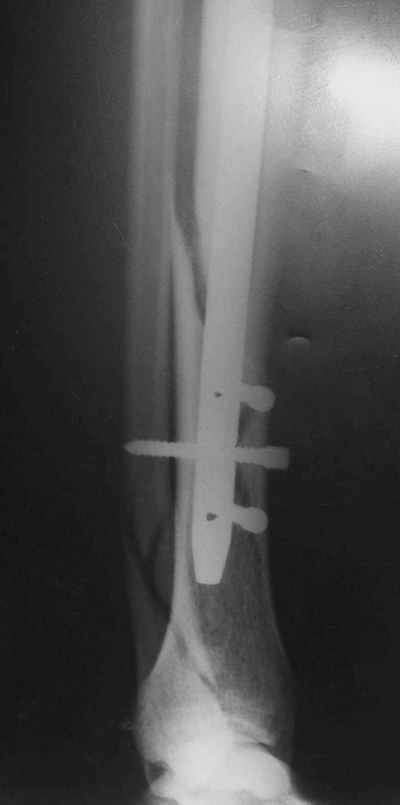

Рентгенограмы

Не удается отправить первичные снимки. А что скажите по имеющимся?!

Выполненный остосинтез нестабилен. Штифт надо заменить по "размеру" на солидный, дистльно три запирающих винта. Успехов!

Перелом спиральный, то есть низкоэнергетический, так что со сращением дело обстоит уже неплохо, лишь бы "костоеда" не развилась. Отломки выглядят уже стабилизированными костной мозолью, так что довводить винты, наверно, уже незачем. Разве что при клинической оценке подвижность еще есть - тогда можно для стабилизации наложить простейший аппарат, не опасаясь контакта его элементов с гвоздем, поскольку места в дистальном метафизе оставлено более чем достаточно.

С Александром согласен, нет необходимости делать дополнительные усилия для сращения, не большая компрессия аппаратом из двух колец и полная нагрузка доделает работу.

Уже имеется какое-то сращение. А в этих условиях выполнить реостеосинтез гвоздём не дольше, чем "накинуть" аппарат из двух колец. Ходить можно сразу с полной нагрузкой, да и качество жизни пациента без аппарата лучше.